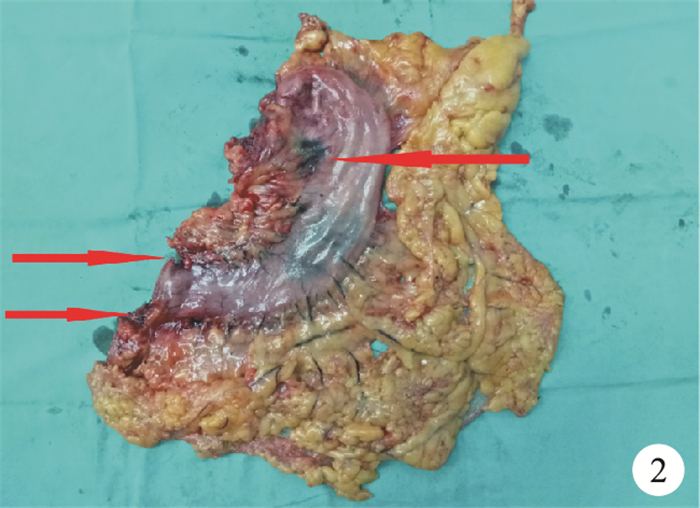

手術均由同一組腹腔鏡胃腸手術經驗豐富的醫師按照胃癌D2根治術標準施行。標本離體后由專人負責解剖以檢出淋巴結(圖 2)。記錄每例檢出淋巴結直徑、數目及檢出時間,納米碳組還需記錄淋巴結黑染情況。2組標本常規行HE染色,顯微鏡下觀察淋巴結轉移情況。

圖2

示離體標本中黑染的淋巴結(紅箭)